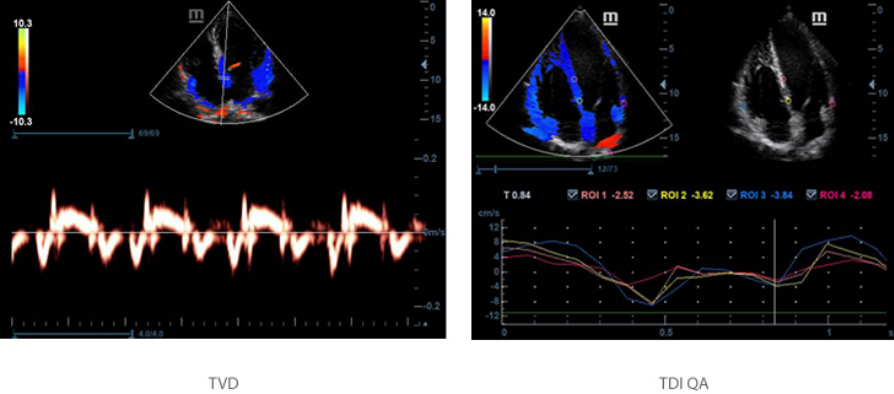

Secara akurat menilai gerakan miokardial pada berbagai tahapan, dan sekaligus menentukan sinkronisasi miokardial. Laju bingkai yang lebih tinggi memberi Anda hasil yang akurat.

TDI & TDI QA

Tissue Doppler Imaging (TDI) memungkinkan Anda secara kuantitatif mengevaluasi fungsi dan gerakan miokardial lokal, dengan parameter kecepatan kuantitatif di TDI QA.